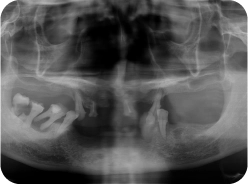

• Jawbone resorption and many teeth lost

A long period of neglecting oral hygiene and smoking had led Mr. Hai to suffering from severe periodontitis. Gradually, this resulted in jawbone resorption and extensive tooth loss in both jaws.

To tackle Mr. Hai problems, Dr. Tin conducted periodontal treatment and extracted the decayed teeth to prevent the infection. He then recommended an All-on-4 implant solution, placing four implants in each jaw to restore both aesthetics and chewing function.